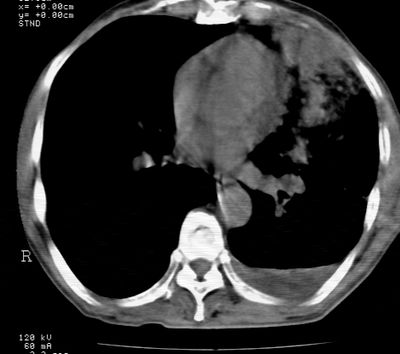

标题: CT24000:M65,胸痛,胸闷月余,既往慢支,肺气肿,肺心病 [打印本页]

标题: CT24000:M65,胸痛,胸闷月余,既往慢支,肺气肿,肺心病

左肺门肿块,相应支气管闭塞,左肺上叶、舌叶大片及散在高密度影,部分呈不张改变,两肺纹粗乱,左侧胸腔积液。考虑左侧中央型肺癌伴阻塞性改变。

左肺门见巨大软组织肿块影,直径约--,境界清,左上肺叶支气管变窄,左上肺舌叶见大片状密实影,余肺纹理增多、紊乱、纤细、部分网格状,两肺透亮度增高,纵隔内见增大多发淋巴结影,心影略左偏,左侧少量胸腔积液。

左侧中央型肺癌伴左上肺舌叶不张、纵隔淋巴结转移,左侧少量胸腔积液。